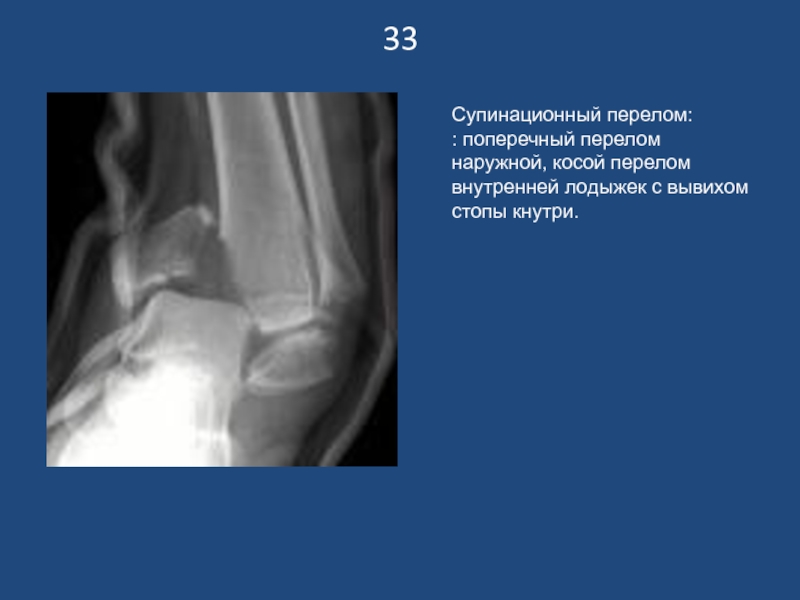

Супинационный перелом:

: поперечный перелом наружной, косой перелом внутренней лодыжек с

вывихом стопы кнутри.

33Супинационный перелом:: поперечный перелом наружной, косой перелом внутренней лодыжек с вывихом стопы кнутри.